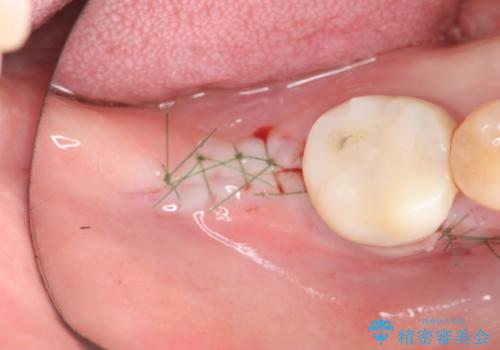

奥歯 インプラントによる機能回復

- 歯を欠損し、噛めないことの治療を希望され来院されました。

インプラントを用いて、しっかりとかめるような治療を計画します。

- 外科手術のため、術後に痛みや腫れ、違和感を伴います